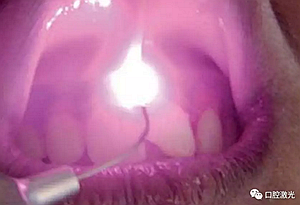

患者22歲,女性,主訴牙齦發(fā)黑??谇粰z查顯示牙齦部位呈黑色,但軟組織健康,沒有表皮粗糙或水腫現(xiàn)象。計(jì)劃使用半導(dǎo)體激光進(jìn)行治療。手術(shù)前患者無需表麻或局麻。采用光纖接觸方式,激光功率設(shè)定為1.5W至2W,連續(xù)模式。氣化黑色牙齦區(qū)域上皮組織。不斷重復(fù)該過程,直至足夠深度的牙齦軟組織表皮被去除干凈?;颊咝g(shù)后需采用漱口水進(jìn)行口腔護(hù)理。

術(shù)中